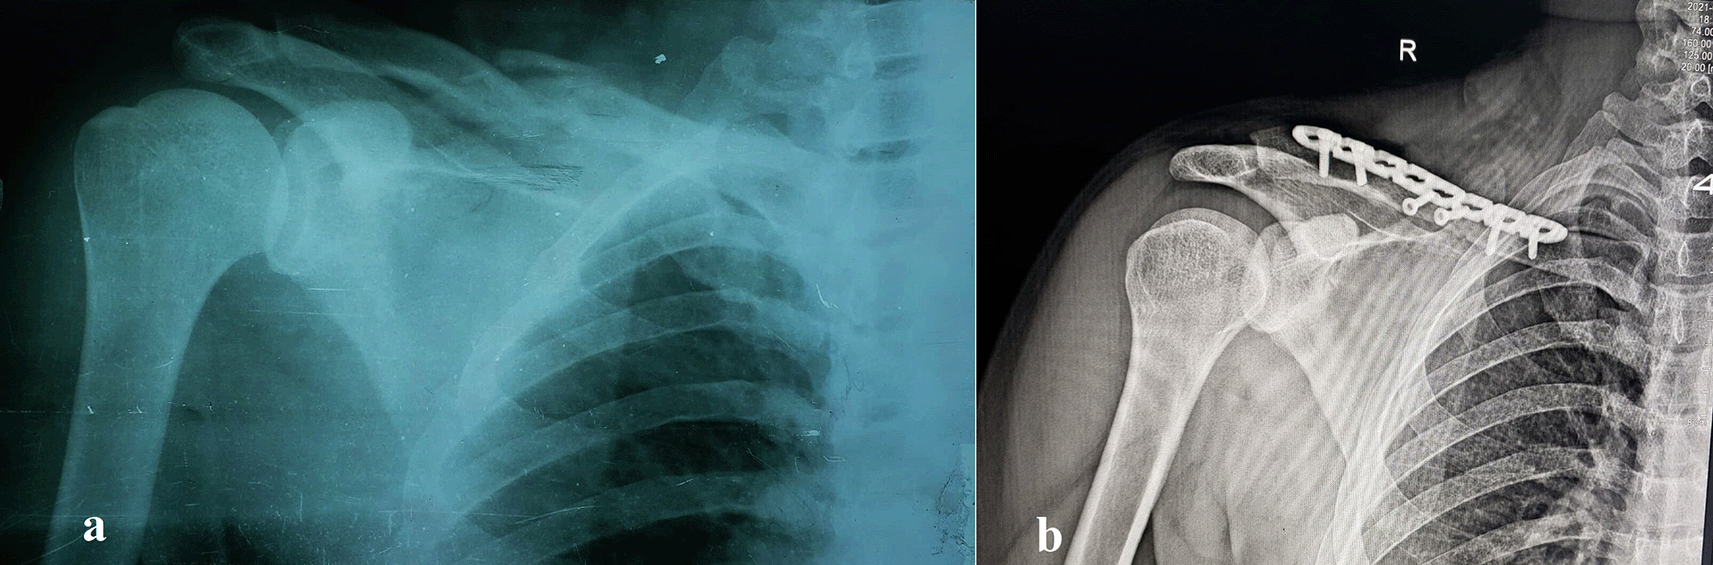

Sixty-five patients with displaced midshaft clavicular fractures treated with precontoured locked plates were enrolled. The mean age was 32.09 years (range: 19–50 years), with 54 males (83.1%) and 11 females (16.9%). Road traffic accidents (RTAs) caused the most injuries (n=43, 66.2%), followed by falls (n=22, 33.8%). The right clavicle was affected in 43 (66.2%) patients and the left clavicle in 22 (33.8%). Table 1 details these traits, and Figures 1–2 show representative cases.

(a) Preoperative anteroposterior radiograph showing a displaced, severely comminuted midshaft fracture of the right clavicle in a 26-year-old female patient. (b) Postoperative anteroposterior radiograph of the same patient following open reduction and internal fixation (ORIF) with a pre-contoured superior locking plate (Orthomed E, 8-hole, titanium). Note the anatomical reduction of the fracture and the use of locking screws that engage at least four cortices on either side of the fracture. Two lag screws were used to stabilize the butterfly fragments.